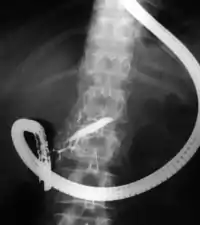

Endoscopic retrograde cholangiopancreatography (ERCP) is a technique that combines the use of endoscopy and fluoroscopy to diagnose and treat certain problems of the biliary or pancreatic ductal systems. It is primarily performed by highly skilled and specialty trained gastroenterologists. Through the endoscope, the physician can see the inside of the stomach and duodenum, and inject a contrast medium into the ducts in the biliary tree and pancreas so they can be seen on radiographs.

The patient is sedated or anaesthetized. Then a flexible camera (endoscope) is inserted through the mouth, down the esophagus, into the stomach, through the pylorus into the duodenum where the ampulla of Vater (the union of the common bile duct and pancreatic duct) exists. The sphincter of Oddi is a muscular valve that controls the opening to the ampulla. The region can be directly visualized with the endoscopic camera while various procedures are performed. A plastic catheter or cannula is inserted through the ampulla, and radiocontrast is injected into the bile ducts and/or pancreatic duct. Fluoroscopy is used to look for blockages, or other lesions such as stones.

When needed, the sphincters of the ampulla and bile ducts can be enlarged by a cut (sphincterotomy) with an electrified wire called a sphincterotome for access into either so that gallstones may be removed or other therapy performed.

Other procedures associated with ERCP include the trawling of the common bile duct with a basket or balloon to remove gallstones and the insertion of a plastic stent to assist the drainage of bile. Also, the pancreatic duct can be cannulated and stents be inserted. The pancreatic duct requires visualisation in cases of pancreatitis.